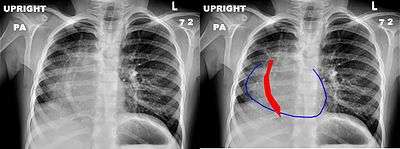

Scimitar syndrome, or pulmonary venolobar syndrome, is a rare congenital heart defect characterized by anomalous venous return from the right lung (to the systemic venous drainage, rather than directly to the left atrium).[1] This anomalous pulmonary venous return can be either partial (PAPVR) or total (TAPVR). The syndrome associated with PAPVR is more commonly known as Scimitar syndrome after the curvilinear pattern created on a chest radiograph by the pulmonary veins that drain to the inferior vena cava.[2] This radiographic density often has the shape of a scimitar, a type of curved sword.[2]

The anomalous venous return forms a curved shadow on chest x-ray such that it resembles a scimitar. This is called the Scimitar Sign. Associated abnormalities include right lung hypoplasia with associated ()dextroposition of the heart, pulmonary artery hypoplasia and pulmonary sequestration.